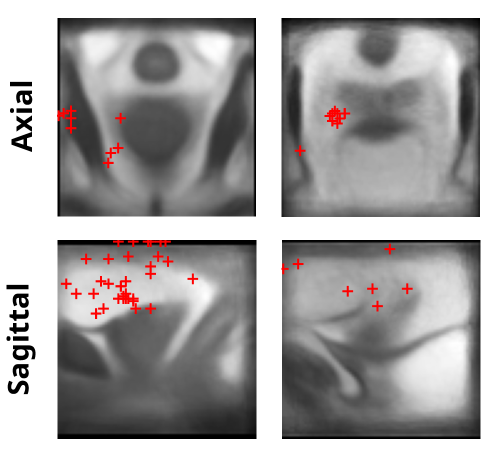

Figure 4: Saliency map on an atlas. The atlas was built from F1F_{1} of all patients in the test data. The visualized heatmap is the mean of saliency maps for all patients in the test data, obtained from All-pairs model inference on F1F_{1}-FLF_{L} pairs and transformed into the atlas space. Column titles indicate the slice orientations (axial, sagittal) and the primary regions of interest highlighted by the saliency maps, although these regions span multiple organs.

Modified Grad-CAM[23, 13] based saliency maps were used to interpret which regions contribute to the model’s predictions. According to the radiologist’s evaluation, the saliency peaks most frequently occurred in the bladder lumen (20.53%) and pubic symphysis (19.21%), with the prostate commonly involved (Table 3). Group-level visualization of the heatmaps on the atlas of all patients is shown in Figure 4 (Peak distribution of the heatmaps in Supplementary Figure A4), of which the primary peak regions are the pubic symphysis and bladder, while the area spans multiple anatomical regions, including the prostate.